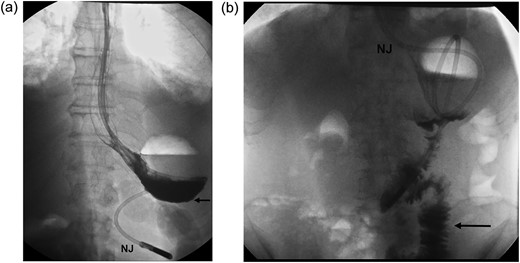

A 70-year-old Asian male underwent radical subtotal gastrectomy and D2 lymphadenectomy for TcisN0M0 gastric carcinoma. High naso-gastric output continued to Day 7. Contrast study showed hold up at the level of the anastomosis between the stomach and the Roux-en-Y gastro-jejunostomy (Fig. 2a). Intravenous dexamethasone at 8 mg daily was instituted for 72 h. Repeat contrast study showed good integrity of the anastomosis (Fig. 2b) and fluid diet was instituted. The patient was discharged 4 days after dexamethasone treatment and normal diet was established.

(a) An upper gastrointestinal series revealing hold up of contrast at the level of gastro-jejunostomy (black arrow), Day 7 post radical subtotal gastrectomy (b) A repeat contrast study, following dexamethasone challenge, shows good emptying with contrast reaching the jejunum (black arrow) promptly (NJ=naso-jejunal feeding tube).